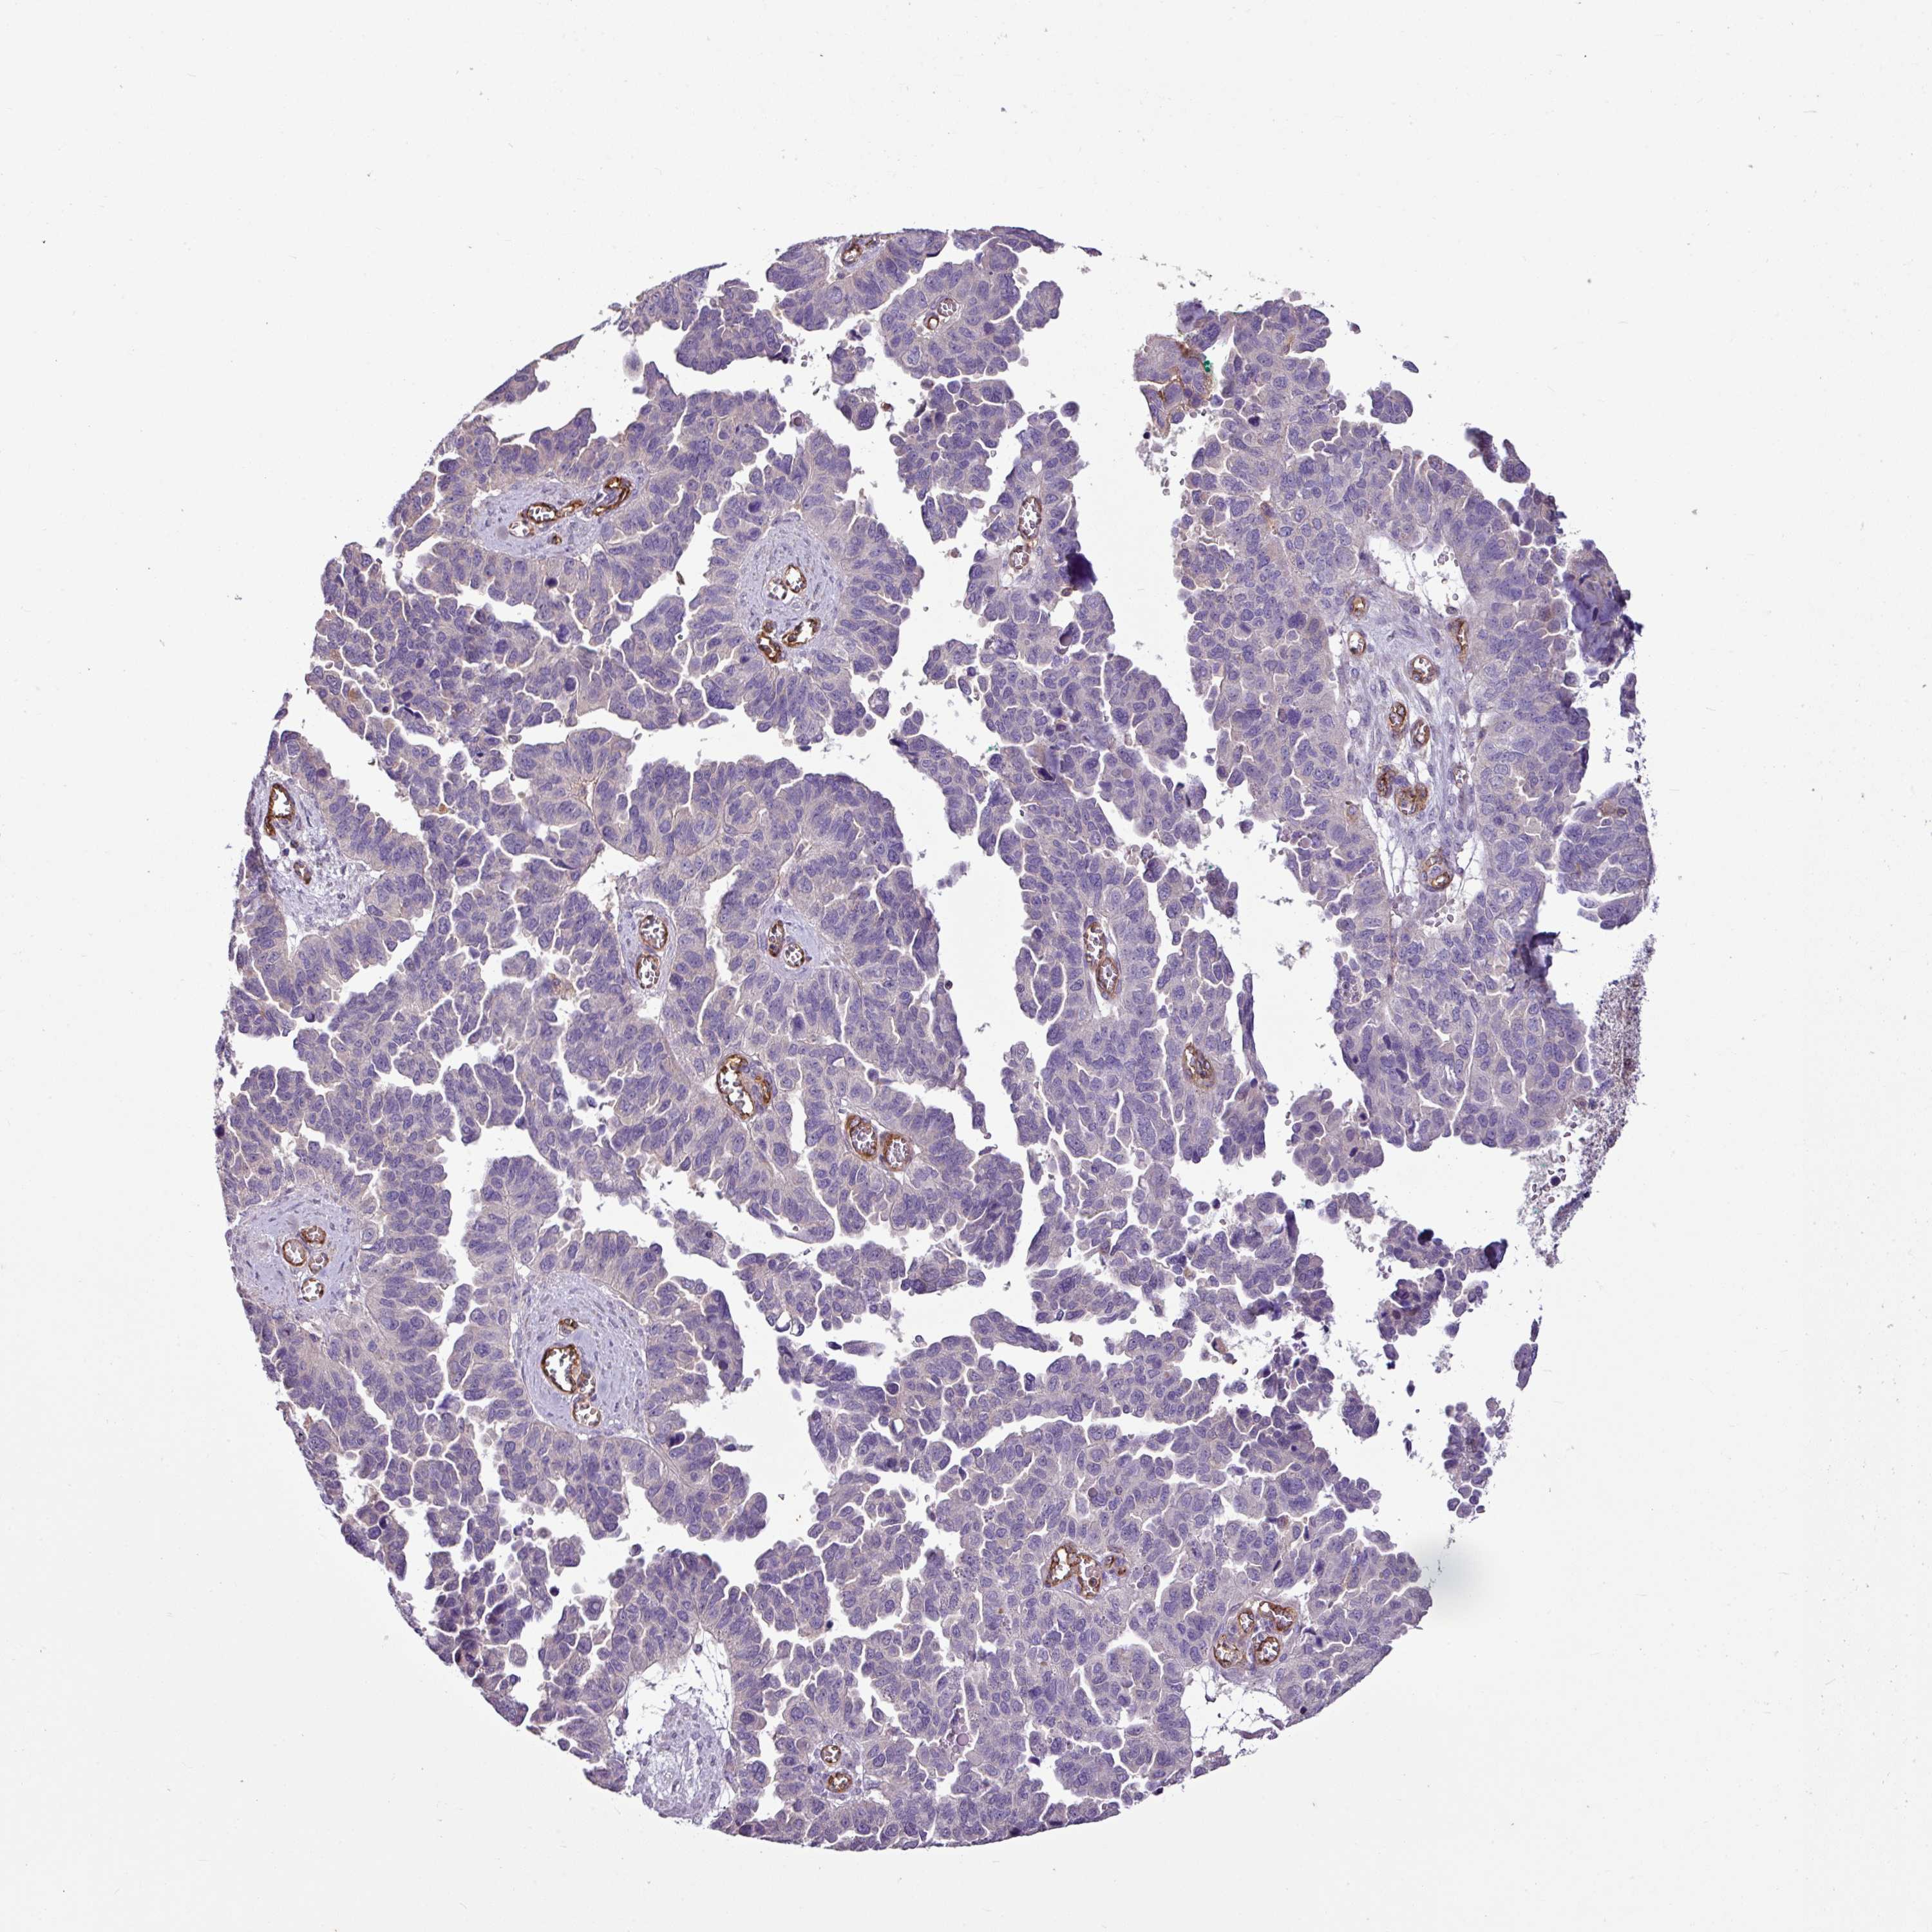

OVARIAN CANCER - Protein expressioni

A mouse-over function shows sample information and annotation data. Click on an image to view it in a full screen mode. Samples can be filtered based on level of antibody staining by selecting one or several of the following categories: high, medium, low and not detected. The assay and annotation is described here.

Note that samples used for immunohistochemistry by the Human Protein Atlas do not correspond to samples in the TCGA dataset.

Antibody stainingi

Antibody staining in the annotated cell types in the current human tissue is reported as not detected, low, medium, or high, based on conventional immunohistochemistry profiling in selected tissues. This score is based on the combination of the staining intensity and fraction of stained cells.

Each image is clickable and will lead to virtual microscopy that enables deeper exploration of all samples and also displays staining intensity scores, fraction scores and subcellular localization as well as patient and tissue information for each sample.

Antibody HPA054267

Staining

High

Medium

Low

Not detected

Intensity

Strong

Moderate

Weak

Negative

Quantity

>75%

75%-25%

<25%

None

Location

Nuclear

Cytoplasmic/membranous

Cytoplasmic/membranous,nuclear

Cystadenocarcinoma, serous, NOS

Cystadenocarcinoma, mucinous, NOS

Adenocarcinoma, NOS

Carcinoma, endometroid